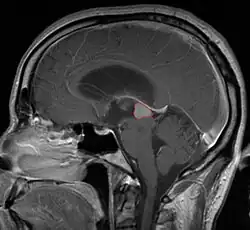

Radiation Oncology/CNS/Pineal

Pineal Gland Tumors

Clinical Presentation

• Determined by the spatial anatomy and direction of growth

• Obstruction of aquaduct: hydrocephalus presenting as headaches, nausea, vomiting

• Compromise of superior colliculus: vertical gaze palsy, pupillary and oculomotor nerve paresis (Parinaud syndrome)